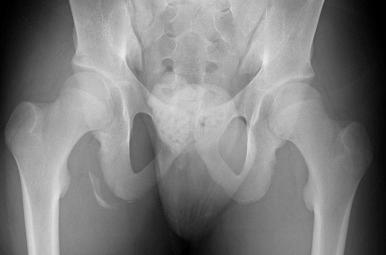

No initial imaging is indicated for hamstring injuries involving no loss of strength and minimal to moderate pain, especially if discomfort is isolated to the muscle belly. If pain is more severe and located proximally, plain radiographs including an anteroposterior view of the pelvis and lateral image of the affected hip are warranted to rule out and characterize an avulsion injury. If a fracture is identified, computed tomography (CT) or magnetic resonance imaging (MRI) may assist in assessing the displacement and fracture configuration for possible surgical planning. Special consideration should be given to obtaining radiographs in the younger patient at risk for apophyseal injuries ( Fig. 86.2 ).

Fig. 86.2, An anteroposterior radiograph of the pelvis showing a bony avulsion of the right ischial tuberosity.